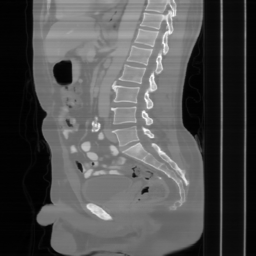

| Ground Truth | Input | DDS-100 [chungdecomposed] | DDS-200 [chungdecomposed] | NERD-P (Ours) |

| PSNR = dB | PSNR = 14.56 dB | PSNR = 37.42 dB | PSNR = 37.81 dB | PSNR = 39.15 dB |

![]() |

| PSNR = dB | PSNR = 15.58 dB | PSNR = 34.28 dB | PSNR = 34.67 dB | PSNR = 35.83 dB |

| PSNR = dB | PSNR = 12.43 dB | PSNR = 36.20 dB | PSNR = 36.56 dB | PSNR = 37.23 dB |

Main results: In Table 1, we present quantitative results and in Figure 2, we show visualizations in the axial, coronal, and sagittal planes. Our methods consistently outperform the second-best baseline across most views, achieving nearly 1 dB higher PSNR on average. Despite incorporating a few additional input updates to enforce data consistency, our method reaches competitive performance with only 30 sampling steps. Based on the visualizations, we observe that DDS introduces slight artifacts along the horizontal direction, particularly noticeable in the coronal and sagittal views. In contrast, our method produces cleaner reconstructions with fewer artifacts in these orientations.